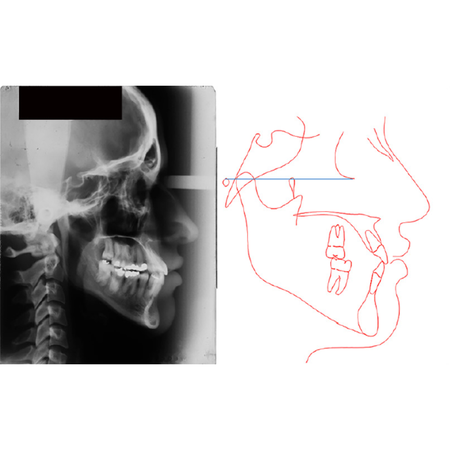

Facial profile attractiveness in orthodontically treated Class III malocclusion patients: a comparison of extraction and non-extraction protocols

Introduction: The treatment of Class III malocclusion has an important impact on facial and smile esthetics. Objective: To compare the facial profile attractiveness (FPA) of Class III malocclusion patients treated with and without premol...

Esthetics Angle Class III Soft-tissue profile